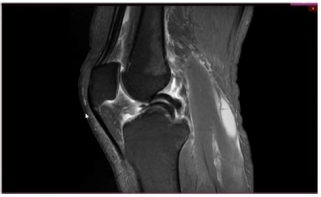

Um paciente de 19 anos de idade sofreu entorse do joelho direito durante agachamento em partida de futebol. Foi retirado do campo e queixando-se de dor na face interna do joelho. Foi levado ao hospital mais próximo e, ao ser examinado, percebeu que não conseguia estender completamente o joelho. Não conseguia flexionar totalmente o joelho também. Notaram-se ainda, edema e o sinal da tecla.

Enunciado 4721093-1

Considere que, no caso clínico descrito, foi realizado o exame complementar, conforme apresentado. Essa figura mostra